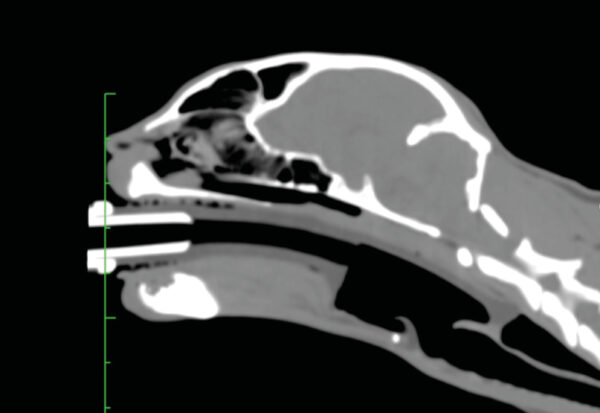

Uno de los dispositivos supraglóticos más utilizados en humana son las mascarillas laríngeas. Aunque al principio se estudió el uso de mascarillas laríngeas de humana en pequeños animales, hace unos años tenemos en el mercado mascarillas laríngeas específicamente diseñadas para la anatomía del gato, el conejo y el perro. La mascarilla laríngea de la especie canina ha sido la última en ser desarrollada y tiene un canal que permite el paso de una sonda para aspirar secreciones esofágicas y disminuir la posibilidad de que el reflujo pase a tráquea (imagen 3).

Su colocación es fácil, ya que solo requiere abrir la boca del animal, estirar la lengua e introducir el dispositivo lubricado hasta que está colocado sobre la entrada de la tráquea (imagen 4). La cúpula queda por encima de las estructuras laríngeas, por lo que, en principio, estas no sufren traumatismo (imagen 5). Para estar seguros de que la colocación es correcta, debemos usar el capnógrafo y observar una curva de capnografía perfecta.

En conejos, debido a su mayor dificultad para intubación endotraqueal comparada con los perros y los gatos, la mascarilla laríngea se ha convertido en una opción tanto para su utilización como dispositivo de manejo de vía aérea como para facilitar la intubación.

Aunque pueden ser de mucha utilidad en pacientes en los que se realicen anestesias cortas o procedimientos poco invasivos (p.ej., TC), debemos tener en cuenta varias limitaciones potenciales. Una de ellas es que, aunque esté correctamente colocada al principio, puede desplazarse si movemos el paciente y dejar, por tanto, una vía de entrada de secreciones a la tráquea, lo que puede dar lugar a complicaciones como neumonía por aspiración, etc. De la misma forma, si la mascarilla está sellando perfectamente la entrada de la tráquea, podemos realizar una perfecta ventilación a presión positiva. Pero, si no está bien sellada, aunque podamos producir una buena ventilación en el paciente, cierto volumen llegará al esófago y estómago, produciendo timpanismo y una mayor posibilidad de reflujo gastroesofágico.